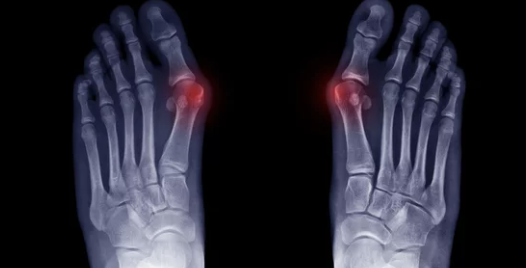

1οΈβ£ μμ§λ°κ°λ½μ΄ νμμ΄μ! π« 무μ§μΈλ°μ¦, λ λꡬλ?

무μ§μΈλ°μ¦μ μμ§λ°κ°λ½μ΄ λ λ²μ§Έ λ°κ°λ½ μͺ½μΌλ‘ νμ΄μ§κ³ , μμ§λ°κ°λ½ κ΄μ μμͺ½μ΄ νμ΄λμ€λ μ§νμ λλ€.

- μμ§λ°κ°λ½ λ³ν: μμ§λ°κ°λ½μ΄ νμ΄μ§λ©΄μ λ° λͺ¨μμ΄ λ³νλκ³ , μ λ°μ μ μ λ λΆνΈν¨κ³Ό ν΅μ¦μ μ λ°ν©λλ€. μ λ μμ μλ νμ΄λμ¨ λΌ λλ¬Έμ μ λ°μ μ μ λλ§λ€ μμ²λ κ³ ν΅μ λκΌμ΅λλ€. π